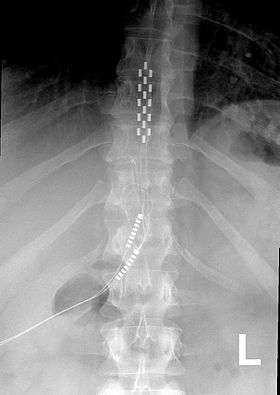

Anterior view X-ray of a spinal cord stimulator (SCS) implanted in the thoracic spine |